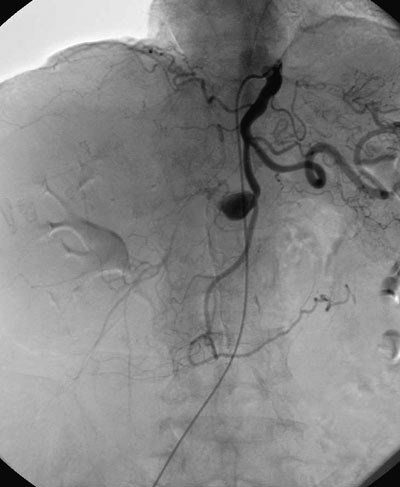

Pasientens kardiale tilstand var nå avklart. De kliniske funnene og plagene var forenlig med det CT-verifiserte aneurismet i a. hepatica. Det var derfor indikasjon for videre utredning med tanke på operativ behandling. I mellomtiden var man imidlertid blitt oppmerksom på at pasienten hadde en bilyd på høyre side av halsen, over arteria carotis. Hun hadde ikke hatt nevrologiske symptomer. Det ble utført MR-angiografi av halskar, som viste en høygradig stenose i høyre a. carotis interna. Venstre a. carotis var normal. Man gikk deretter videre med selektiv digital subtraksjonsangiografi av a. hepatica via truncus coeliacus, med innstikk i lysken. Digital subtraksjonsangiografi regnes som gullstandard for preoperativ utredning av viscerale aneurismer (1).

Digital subtraksjonsangiografi viste åpne forhold til og med den proksimale buklen av aneurismet, med åpen a. gastroduodenalis. Det var tilkommet trombosering av den distale buklen av aneurismet (fig 2). Klinisk var pasientens tilstand uforandret, med symptomer som vi tilskrev aneurismet. Det ble ikke registrert stigning i leverfunksjonsprøver.